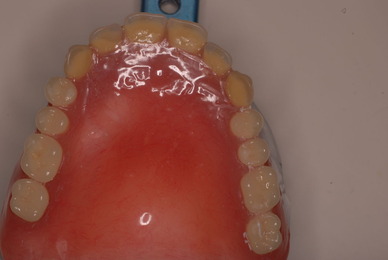

上の総義歯はまっったくはずれませんでした。下顎の入れ歯では若干痛みが出そうなので噛み合わせの調整をしています。口腔内では時間がかかりすぎるので器械に付けて調整しています。

左側の噛み合わせはまともにできます。